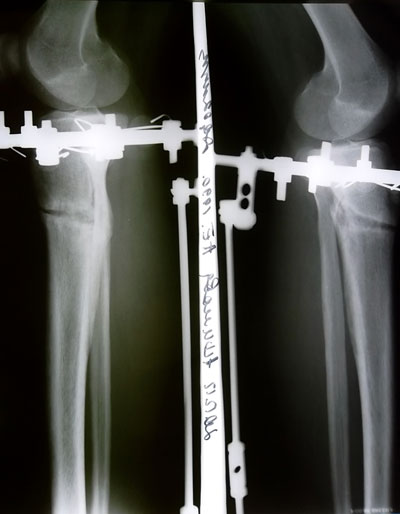

2,5 месяца с момента операции.

Дата операции 27.09.2012г.

Дата снятия аппаратов 26.12.2012г.

Срок лечения 87 дней.